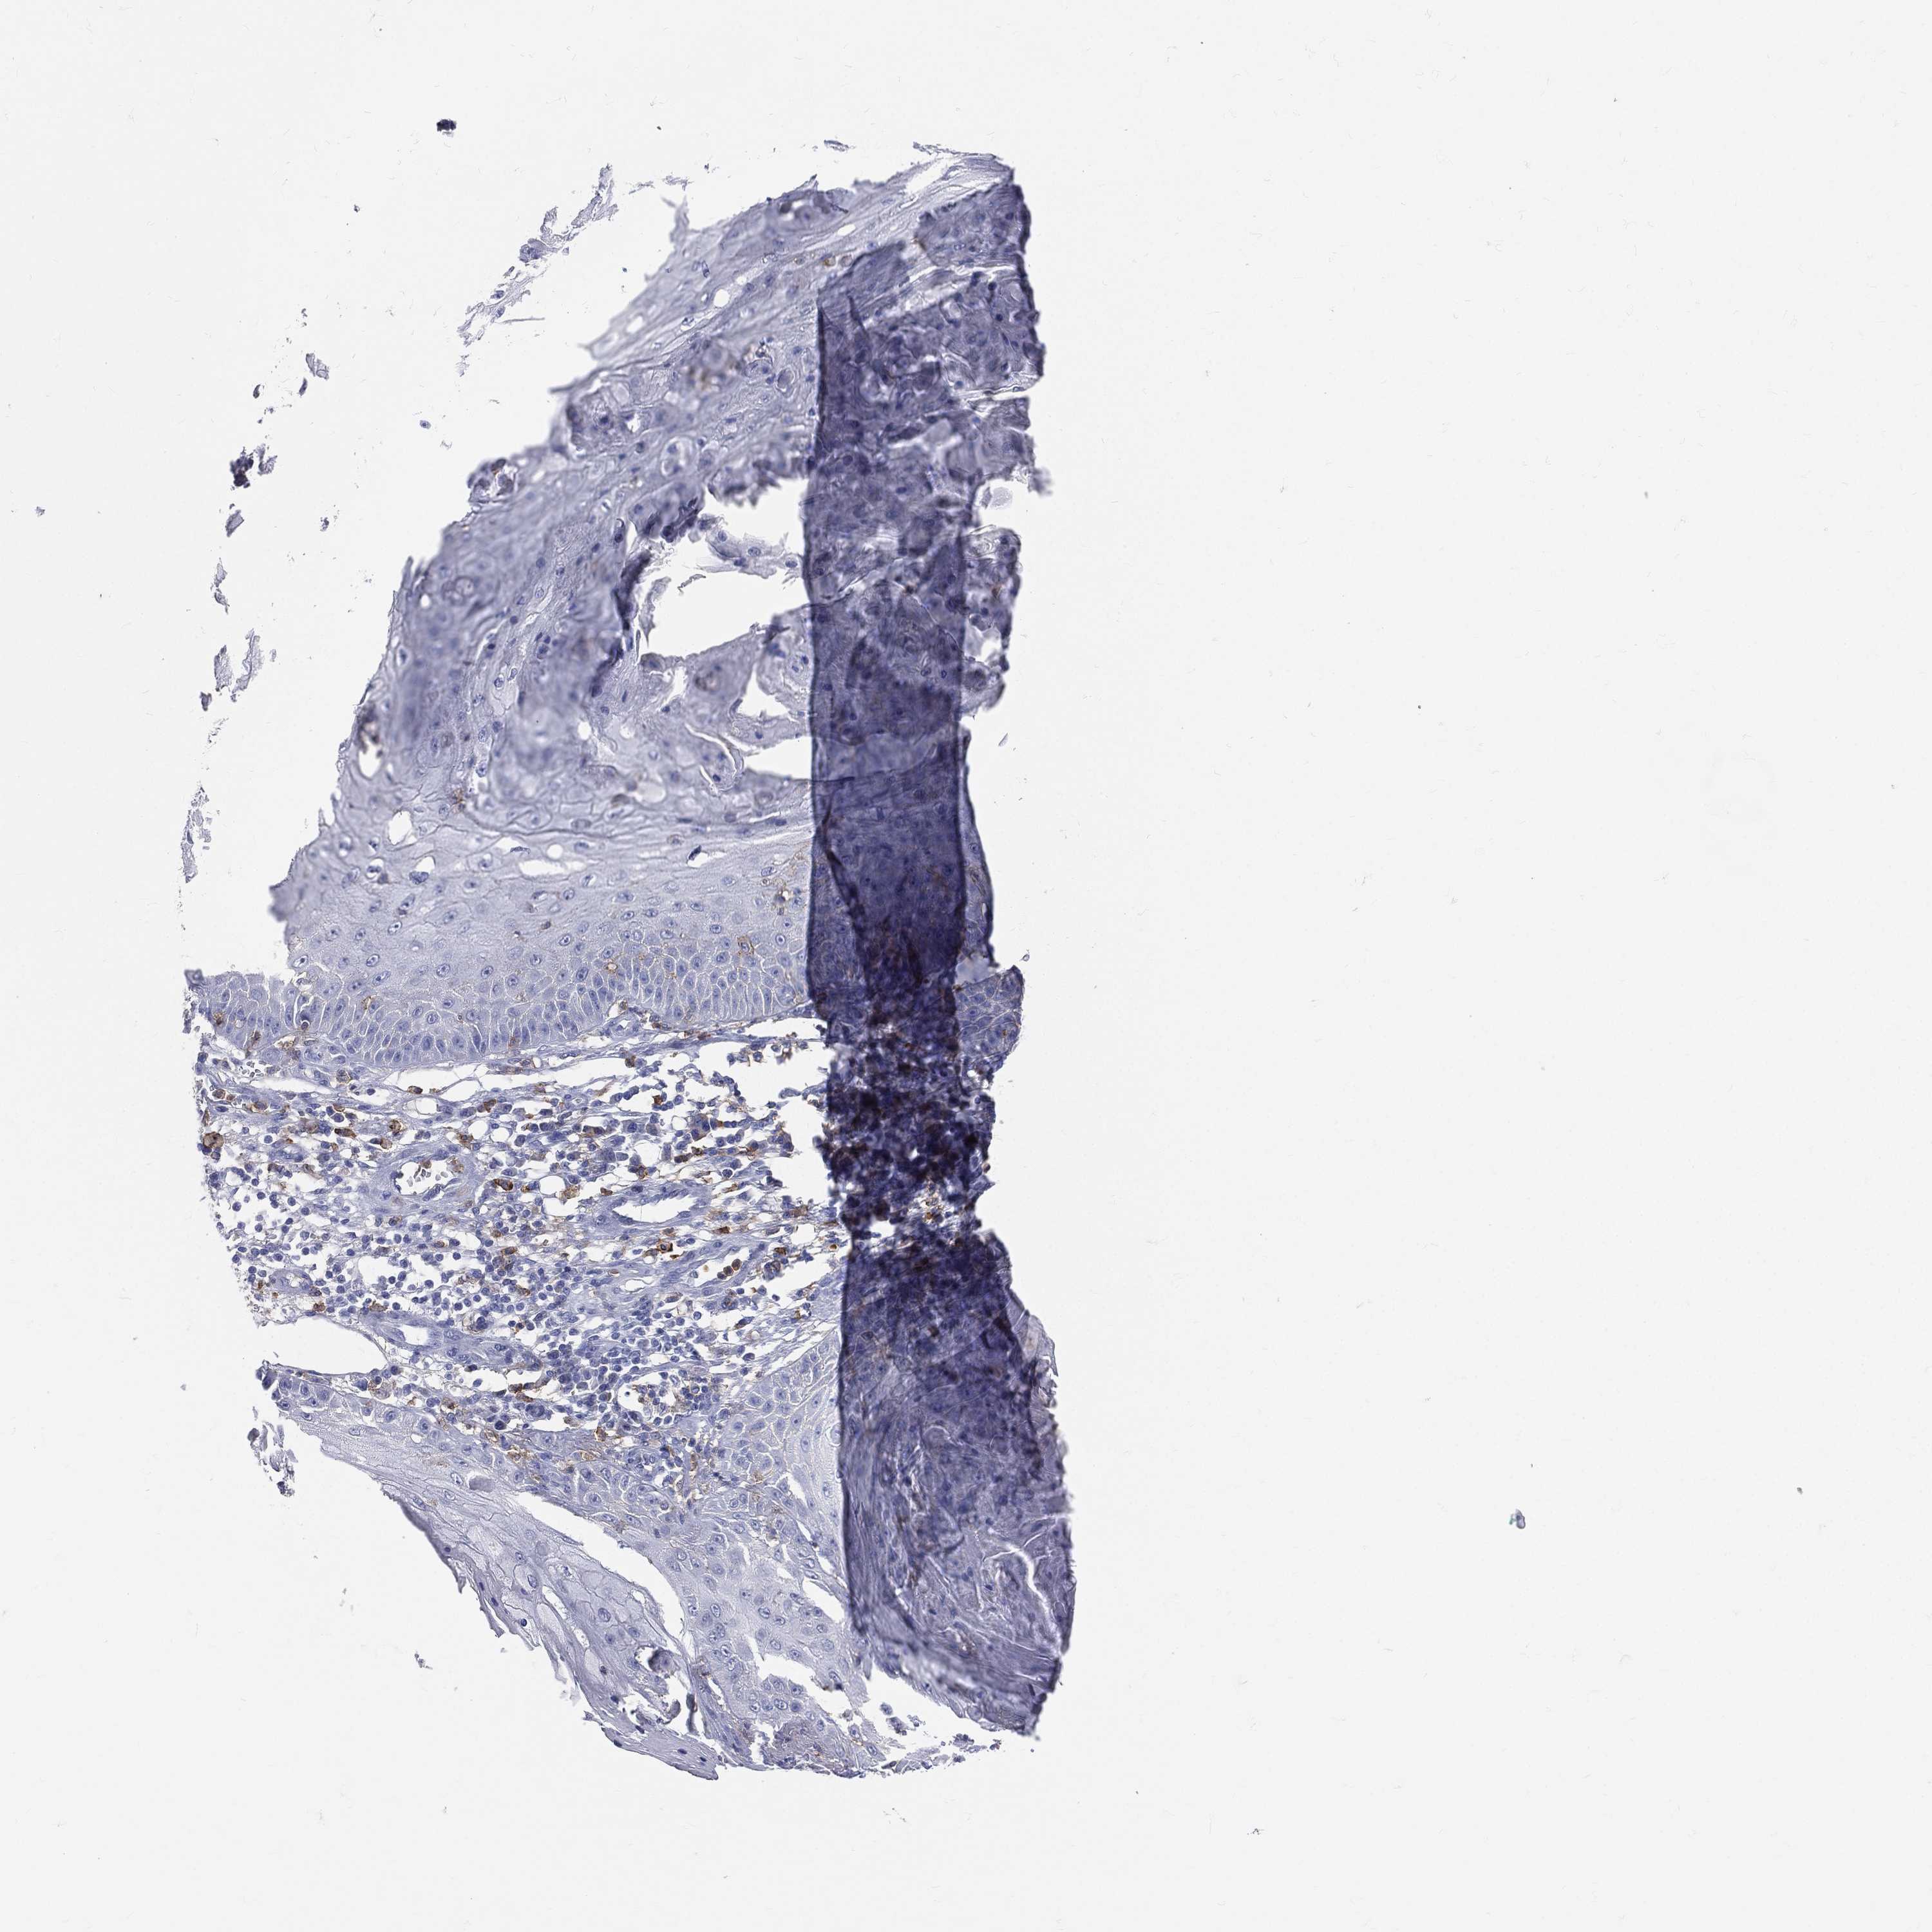

SKIN CANCER - Protein expressioni

A mouse-over function shows sample information and annotation data. Click on an image to view it in a full screen mode. Samples can be filtered based on level of antibody staining by selecting one or several of the following categories: high, medium, low and not detected. The assay and annotation is described here.

Each image is clickable and will lead to virtual microscopy that enables deeper exploration of all samples and also displays staining intensity scores, fraction scores and subcellular localization as well as patient and tissue information for each sample.

Antibody CAB011442

Squamous cell carcinoma, NOS